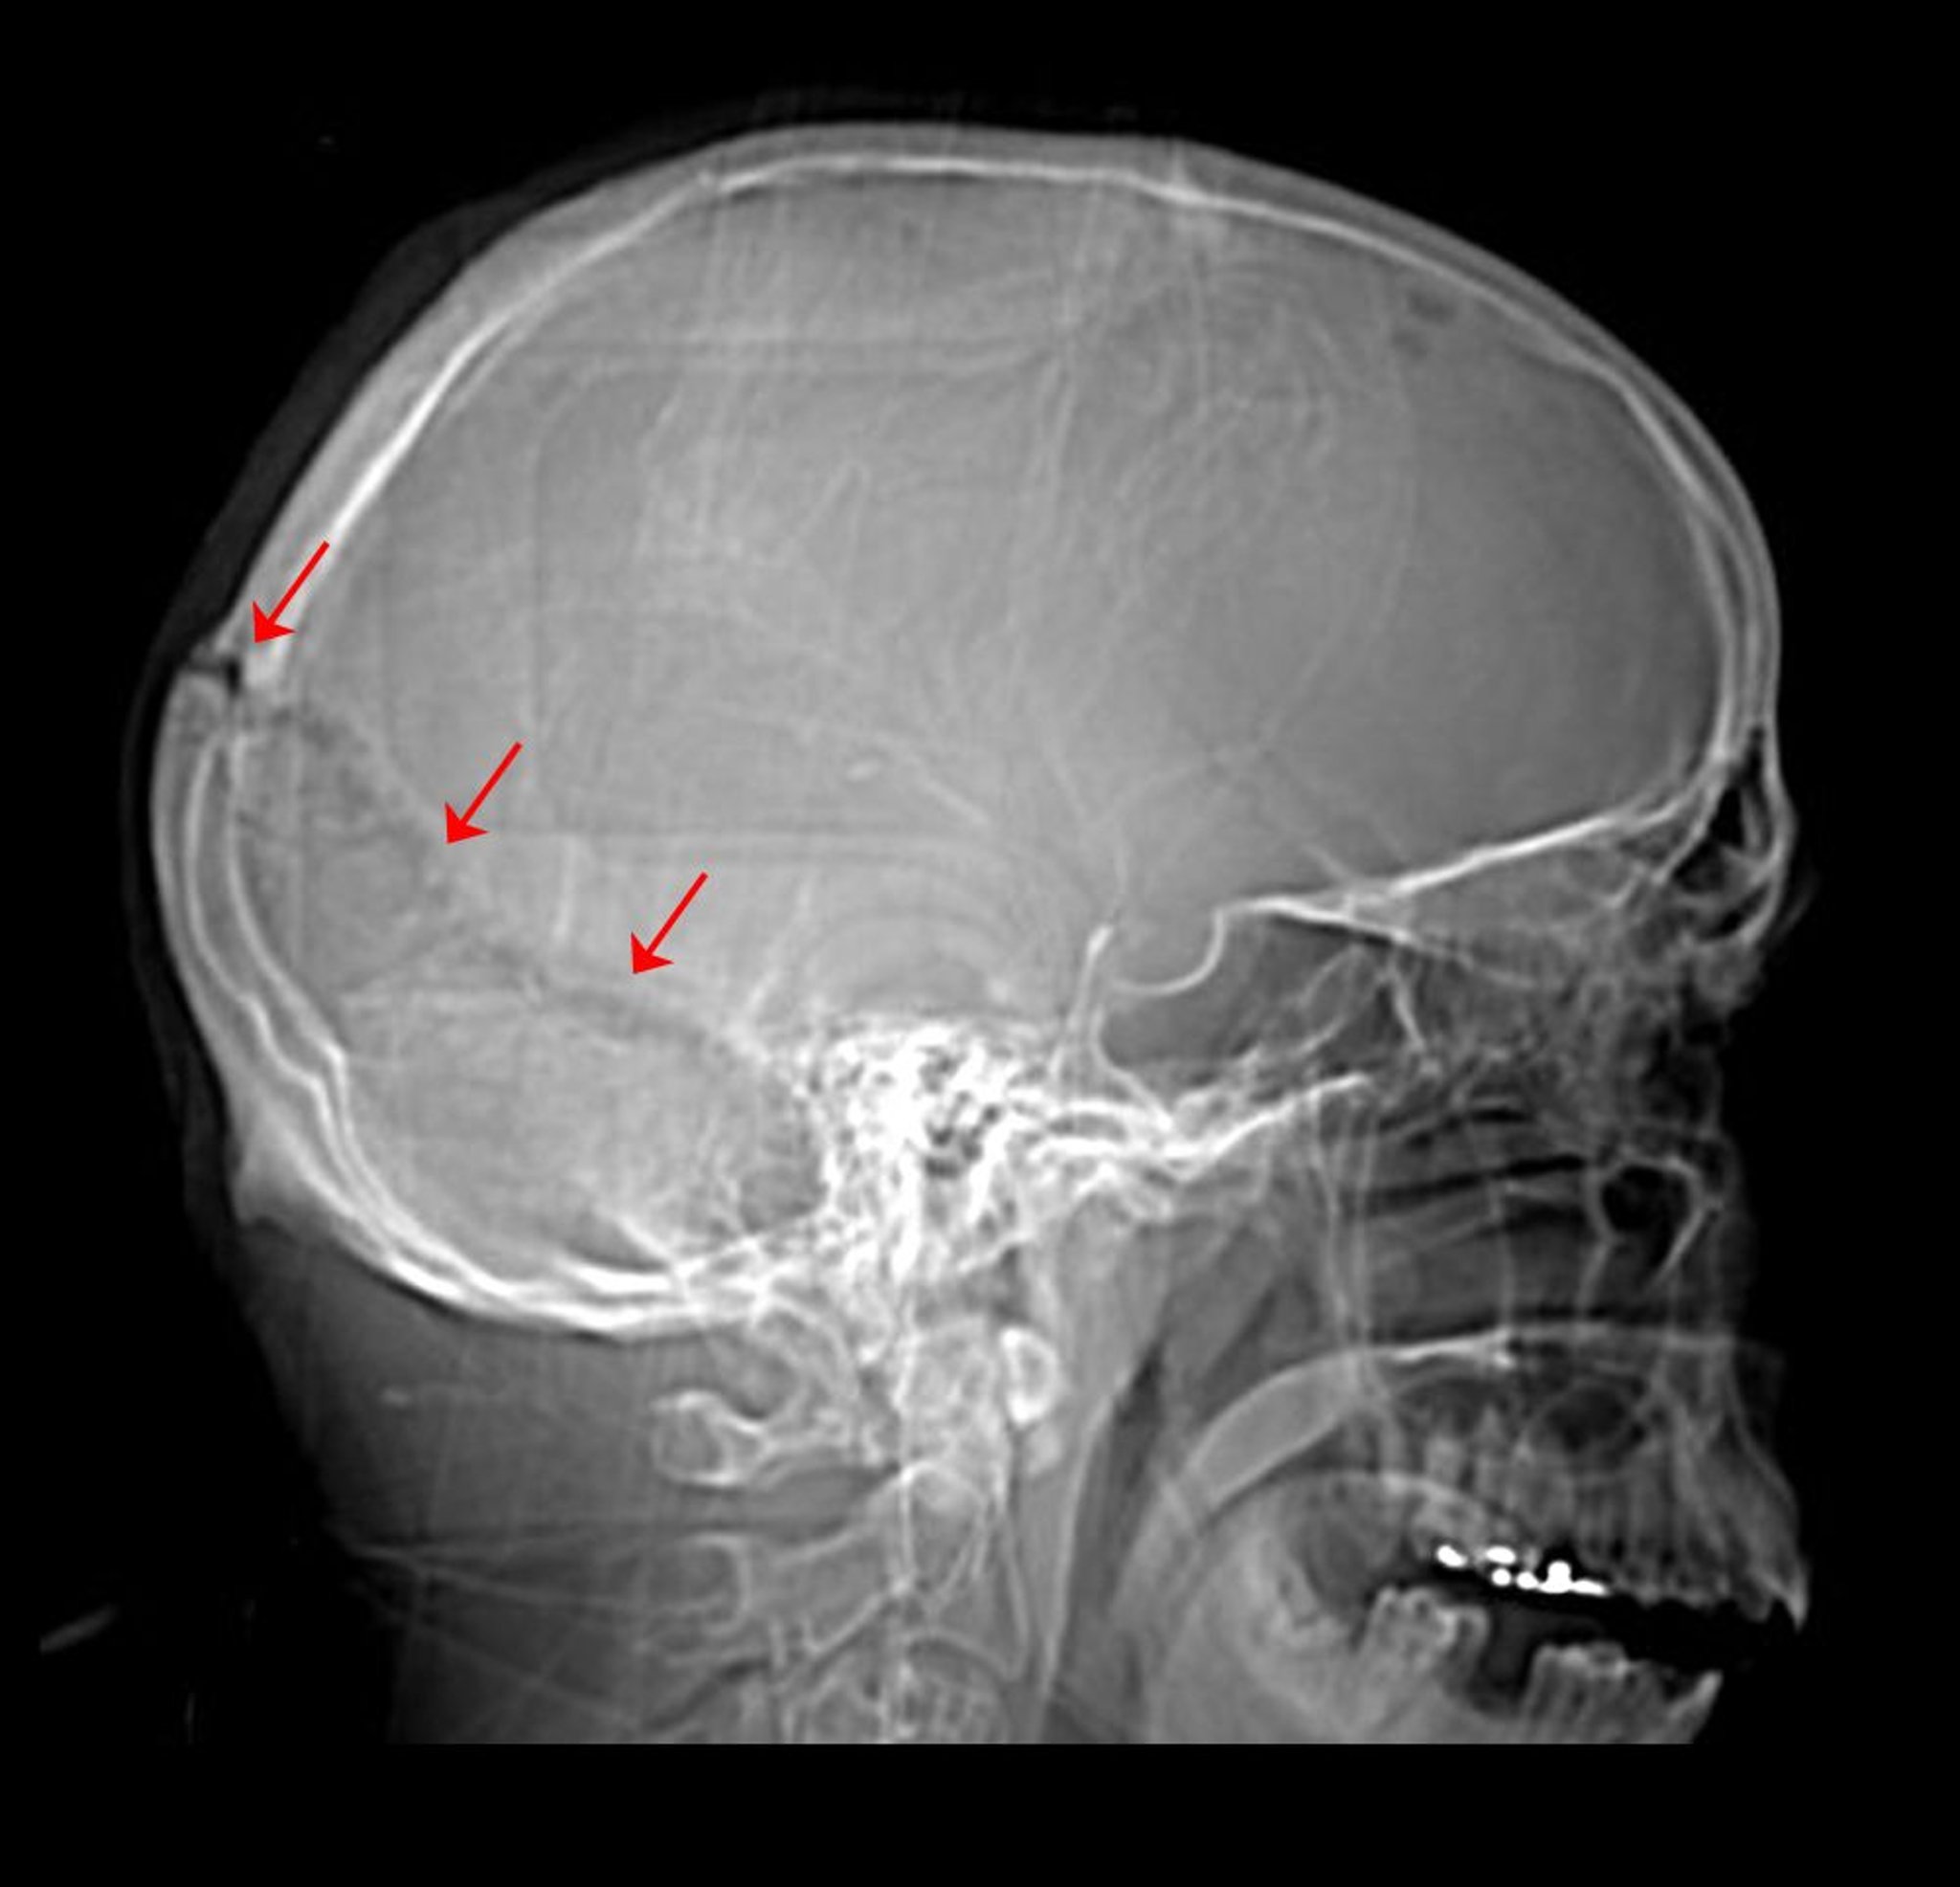

На цій рентгенограмі кісток черепа видно перелом у ділянці лямбдоподібного шва.